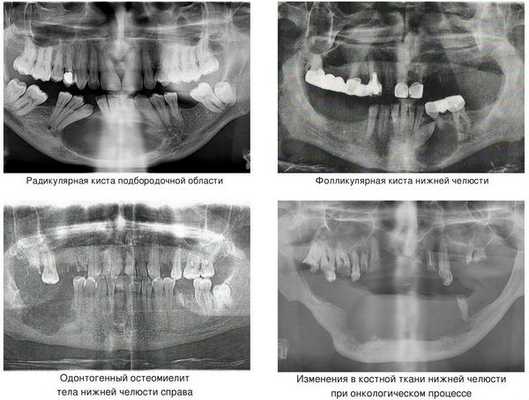

Наиболее частой причиной возникновения перелома нижней челюсти является травматический фактор. В ряде случаев речь может идти о патологическом переломе из-за деструктивных процессов в костной ткани. [1] К таким патологическим процессам относятся:

- кисты челюстей;

- остеомиелит (гнойное воспаление костных тканей);

- онкологический процесс.

Кисты челюстей в основной массе протекают бессимптомно, медленно, но верно разрешая костную ткань. Часто патологический перелом вызвают радикулярные (корневые) и фолликулярные кисты. [2] Первые связаны с изменениями в периапикальных тканях одного или нескольких зубов, вторые являются результатом нарушения прорезывания зубов, чаще нижних зубов мудрости.

При онкологическом процессе нижняя челюсть может быть как первичным очагом, так и местом метастазирования посредством либо прорастания из близлежащих областей, либо распространением с током крови или лимфы. [3] Патологический процесс распространяется до тех пор, пока не разрушит костную ткань нижней челюсти до той стадии, в которой обычное пережевывание пищи может перевести к перелому.

Компьютерная томография (КТ) — самый информативный метод диагностики остеомиелита челюсти. Это 3D-исследование, которое позволяет определить очаг инфекции и степень выраженности воспаления, его длительность и характер. С помощью КТ можно выявить не только крупные, но и мелкие образования, единичные и групповые, а также проанализировать, насколько далеко распространилась инфекция.

Рентгенография в первую неделю, как правило, не выявляет изменения в кости — в этот период воспалена только верхушка корня зуба. К концу второй недели кость разрушается и становится прозрачнее.